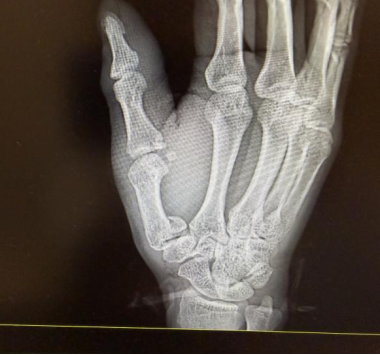

拍片结果印证了刘医生的判断,李先生右手第一掌骨、第一近节指骨基底部都骨折了。刘医生为他的伤口做了清创缝合,随后骨科医生也及时介入,做了临时石膏固定,后续李先生还得住院择期手术。说起这事,李先生满是懊恼,不仅自己受了罪,还把儿子吓得大哭,给孩子留下了心理阴影。